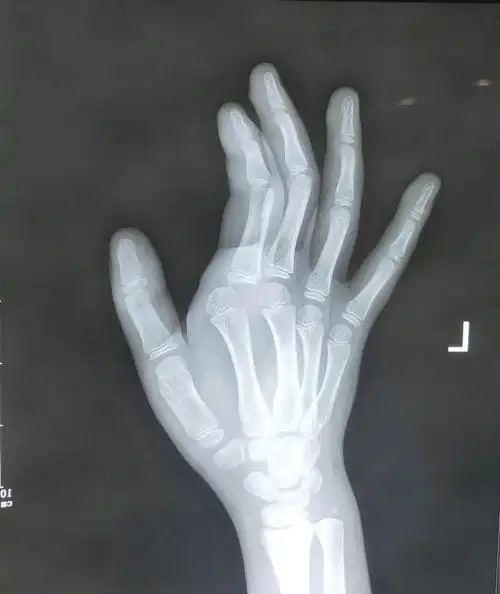

新年夜确是在医院过的,孩子因为在游乐场玩耍造成手指错位,相当严重